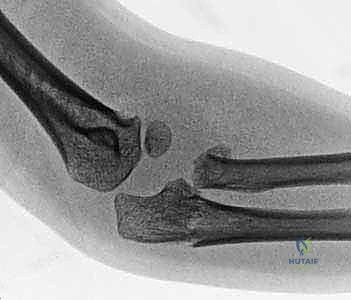

2. التصوير الشعاعي (X-Rays)

هو الخطوة الأساسية لتأكيد الكسر. يتم التقاط صور من زوايا متعددة (أمامية خلفية، وجانبية، ومائلة).

* علامة وسادة الدهون (Fat Pad Sign / Sail Sign): في بعض الأحيان، خاصة في كسور النوع الأول غير المزاحة، قد لا يظهر خط الكسر بوضوح في الأشعة. في هذه الحالة، يبحث الدكتور هطيف عن "علامة الشراع" أو ارتفاع وسادة الدهون المحيطة بالمرفق في الصورة الجانبية، والتي تدل على وجود نزيف مفصلي (Hemarthrosis) يؤكد وجود كسر خفي.